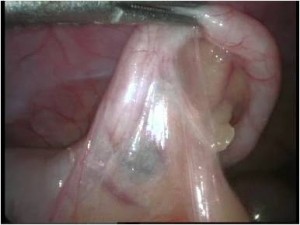

Acute Scrotum

Torsion Testis (Pre and Per operative photo)